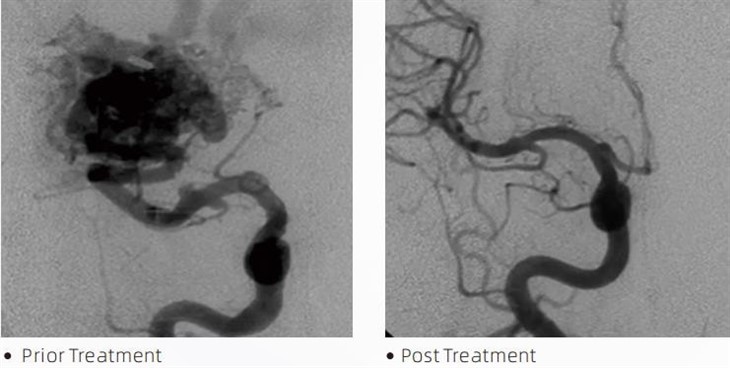

লাভাটিএমএম্বোলিক আঠা একটি মেডিকেল ডিভাইস যা সেরিব্রাল অ্যানিউরিজম, আর্টেরিওভেনাস ম্যালফরমেশন এবং টিউমারের মতো অবস্থার চিকিৎসার জন্য ন্যূনতম আক্রমণাত্মক পদ্ধতির সময় ইন্টারভেনশনাল নিউরোরাডিওলজিস্টদের দ্বারা ব্যবহৃত হয়। লাভা এম্বোলিক আঠালো চিকিৎসা পেশাজীবী এবং রোগীদের নিরাপত্তা, ব্যবহারের সহজতা এবং কার্যকারিতার ক্ষেত্রে একাধিক সুবিধা প্রদান করে। লাভা দ্রুত এবং দক্ষতার সাথে রক্তনালী বন্ধ করতে সক্ষম। প্রক্রিয়াটিতে আঠালোকে সরাসরি লক্ষ্যযুক্ত পাত্রে ইনজেকশন করা জড়িত, যেখানে এটি পলিমারাইজ করে এবং শক্ত হয়ে একটি ঢালাইয়ের মতো ভরে পরিণত হয় যা অ্যানিউরিজম বা বিকৃতি পূরণ করে। তারপরে এটি কার্যকরভাবে ক্ষতটিতে রক্ত প্রবাহ বন্ধ করে, এটি ফেটে যাওয়া প্রতিরোধ করে এবং স্থায়ী ক্ষতি বা স্ট্রোকের ঝুঁকি হ্রাস করে। লাভার মধ্যে রয়েছে লাভা-12, লাভা-18 এবং লাভা-34। প্রতিটি ফর্মুলেশন নির্দিষ্ট ক্লিনিকাল চাহিদা মেটাতে ডিজাইন করা হয়েছে। লাভা-18 হল সাধারণ ব্যবহারের জন্য আদর্শ সূত্র। লাভা-34 উচ্চ প্রবাহবাহী জাহাজের জন্য উচ্চ-সান্দ্রতা আঠালো। যদিও লাভা-12 এর সান্দ্রতা কম এবং এটি আরও প্রবাহযোগ্য, যা দূরবর্তী মাইক্রোভেসলের জন্য অনুমতি দেয়। এই বিকল্পগুলির সাহায্যে, ইন্টারভেনশনাল নিউরোরাডিওলজিস্টরা সর্বোত্তম ফলাফল নিশ্চিত করতে উপযুক্ত লাভা ফর্মুলেশন বেছে নিতে পারেন। লাভার সবচেয়ে উল্লেখযোগ্য বৈশিষ্ট্যগুলির মধ্যে একটি হল এর অ-আঠালো বৈশিষ্ট্য। এই পদার্থটি লক্ষ্যবস্তুতে পৌঁছানো পর্যন্ত স্থিতিশীল থাকার জন্য বিশেষভাবে তৈরি করা হয়। এই বৈশিষ্ট্যটির অর্থ হল লাভা এম্বোলিক আঠা সঠিকভাবে ধমনীর মধ্যে স্থাপন করা যেতে পারে এবং আশেপাশের টিস্যুর সাথে আটকে বা বন্ধন ছাড়াই সেখানে থাকতে পারে।